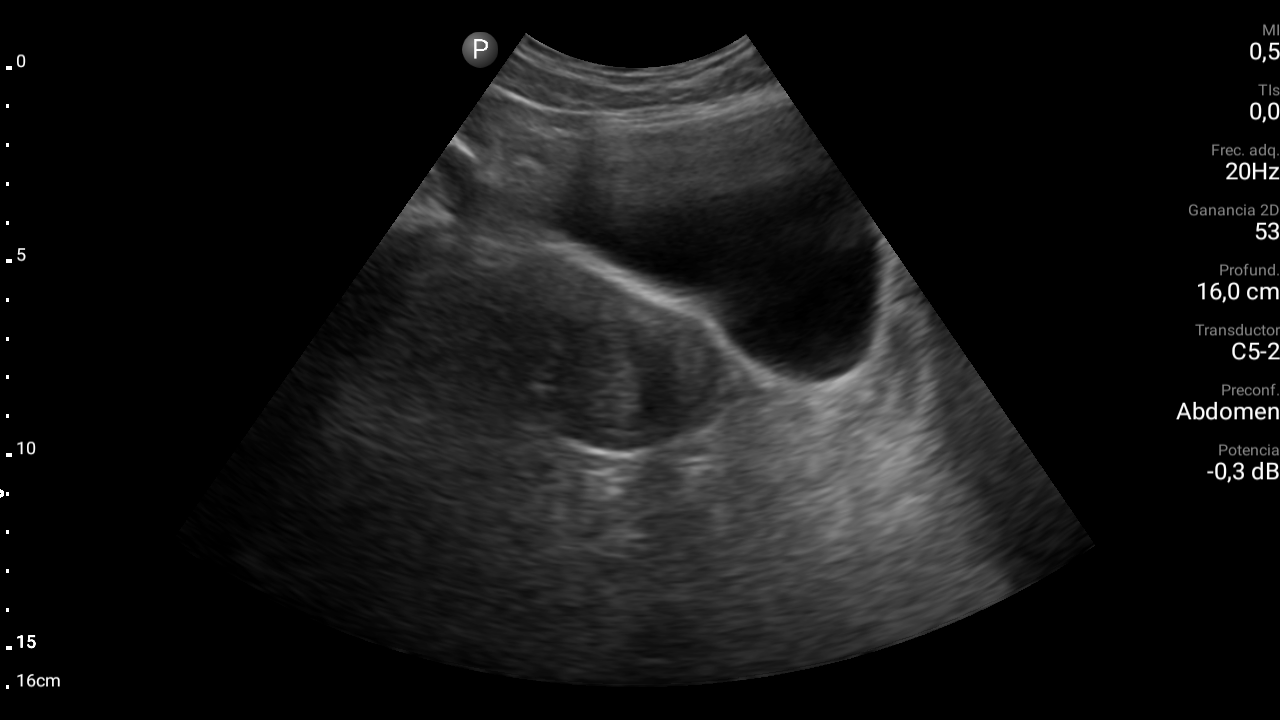

Hallazgos ecográficos

En ecografía abdominal se observa masa hipoecoica dependiente de útero por lo que se remite de forma preferente a ginecología.